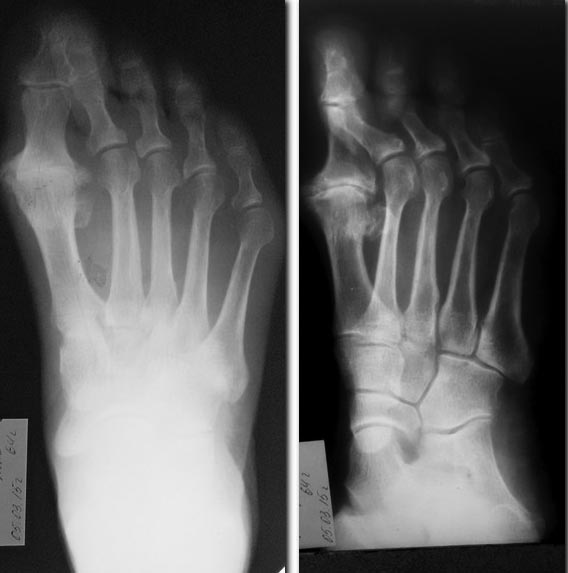

Причем тут Лапидус? Этим именем часто называют артродез первого плюснеклиновидного сустава. А на представленных снимках - артроз первого плюснефалангового сустава. Возможно, Вы имели ввиду его артродез? В принципе, правильно. В сочетании с хейлэктомией головки первой плюсневой и основания основной фаланги. Только по снимкам имеется еще и молоткообразная деформация 2-3(4?) пальцев с перекрестом первого и второго. Нужно продумать, что делать с этим. По-крайней мере, второй палец не должен после операции остаться поверх первого. И вообще важно понять, что беспокоит пациентку. Часто при таких артрозах (жаль, что нет фотографий стопы) ведущие жалобы связаны не с болью в пораженном артрозом суставе, а с наличием массивных костных разрастаний вокруг него. А в данном случае еще и деформации 2 пальца. И может быть в 63 г. пациентке будет достаточно хейлэктомии и устранения деформации 2 пальца?

посмотреть бы педографию - скорее всего, перераспределение зон давления в сторону головок 2-3 лучей. возможно, это может провоцировать боль там при ходьбе.

если "лечить" рентгенограммы, то:

- артродез 1го плюснефалангового сустава с обстоятельным удалением остеофитов;

- дистальная Weil-остеотомия 2 и, возможно, 3 лучей (по рентгену - относительное удлинение минимум второго луча)

- коррекция деформации 2-3 пальцев: PIP-артродез с отделением сухожилий длинных сгибателей как можно дистальнее и пересадкой их кпереди (intrinsic-procedure) с временной трансфиксацией спицами на 6 недель

Жаль, что зафиксировали спицами, а не винтами или пластиной. Спицы сколько продержите? Пять-шесть недель, больше рискованно. А за такой срок анкилоз редко формируется. К тому же, винтами или пластиной можно было создать компрессию суставных поверхностей. И, конечно, второй палец нужно было тоже укорачивать. Из-за укорочения первого луча стопа переведена в ярко выраженный греческий тип. Избыточная длина второго пальца может вызывать неудобство и провоцировать рецидив деформации.